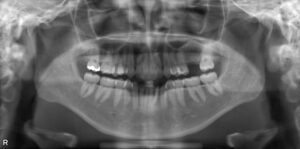

下顎臼歯3本欠損症例

BEFORE AFTER 76歳女性/下3本欠損/インプラント埋込手術 【治療内容】 左下の部分入れ歯が合わずご来院され…